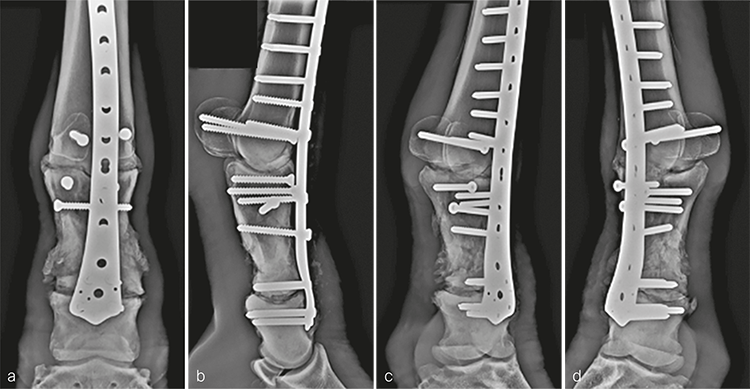

The cast was changed 2 weeks postoperatively and removed 1 month following the repair. The distal limb was maintained in a Robert-Jones bandage for 1 additional month. Routine hoof care in conjunction with rocker shoes and silicone padding were initiated at the time of cast removal. The mare made excellent progress postoperatively and was fully weight bearing on the repaired leg immediately. Radiographic evaluation 5 months postoperatively confirmed good fracture healing and progression of the arthrodesis (Fig 6). The mare was returned to paddock activity at this time and was fully functional with only mild mechanical lameness, as expected with arthrodesis of the metacarpophalangeal joint.

Postanesthetic myopathy complicated the patients recovery and necessitated intensive care immediately following surgery. He responded to supportive therapy and improved rapidly. In addition, his comfort level was excellent on his operated leg for the duration of hospitalization. At 3 months postoperatively, clinical evaluation revealed excellent weight bearing on the operated leg (Fig 8a), with mechanical lameness characteristic of horses with a fused metacarpophalangeal joint. The cosmetic appearance of the distal limb was excellent (Fig 8bc). Radiographic examination demonstrated excellent fracture healing with ongoing progress of the arthrodesis in both articulations (Fig 9). He was shoed with rocking shoes and silicone padding on both front feet to facilitate mobility and to provide hoof support.